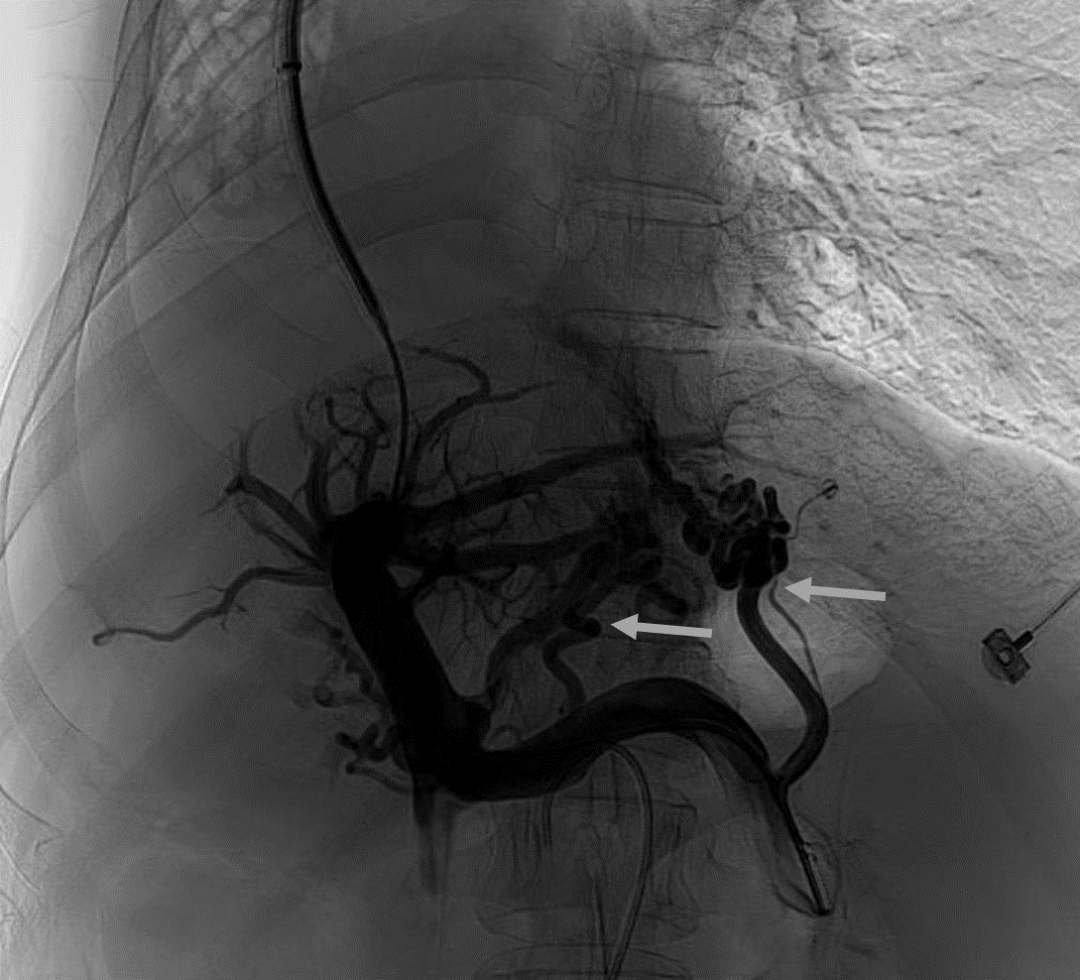

韓國(guó)宏教授介紹,TIPS手術(shù)是通過(guò)在肝靜脈與門靜脈之間的肝實(shí)質(zhì)內(nèi)建立分流通道,通過(guò)降低門靜脈壓力來(lái)預(yù)防和治療因門靜脈高壓引起的食管胃底曲張靜脈破裂出血或頑固性腹水。該手術(shù)不用開(kāi)刀、創(chuàng)傷小、操作過(guò)程復(fù)雜、技術(shù)難度大、安全風(fēng)險(xiǎn)高,是目前外周血管介入中難度最大的手術(shù)之一。再加上人群中右位心發(fā)病率極低(約萬(wàn)分之一),經(jīng)查閱文獻(xiàn),在國(guó)內(nèi)外尚未有類似病例報(bào)道,無(wú)經(jīng)驗(yàn)參考。在右位心基礎(chǔ)上行TIPS術(shù),無(wú)疑是難上加難。我們反復(fù)研究患者肝臟及心血管的特殊情況,詳細(xì)討論了手術(shù)方案,決定放棄常規(guī)的肝靜脈穿刺,另辟蹊徑,選擇高難度高風(fēng)險(xiǎn)的肝后段下腔靜脈穿刺門靜脈左支,憑借多年的經(jīng)驗(yàn)和嫻熟的技術(shù)最終成功的在下腔靜脈與門靜脈之間放置了TIPS專用支架,術(shù)后門靜脈壓力梯度從術(shù)前的19mmHg降至3mmHg,曲張靜脈消失,解決了困擾曹女士多年上消化道出血的困擾?;颊咝g(shù)后第二天即可正常下床活動(dòng)。